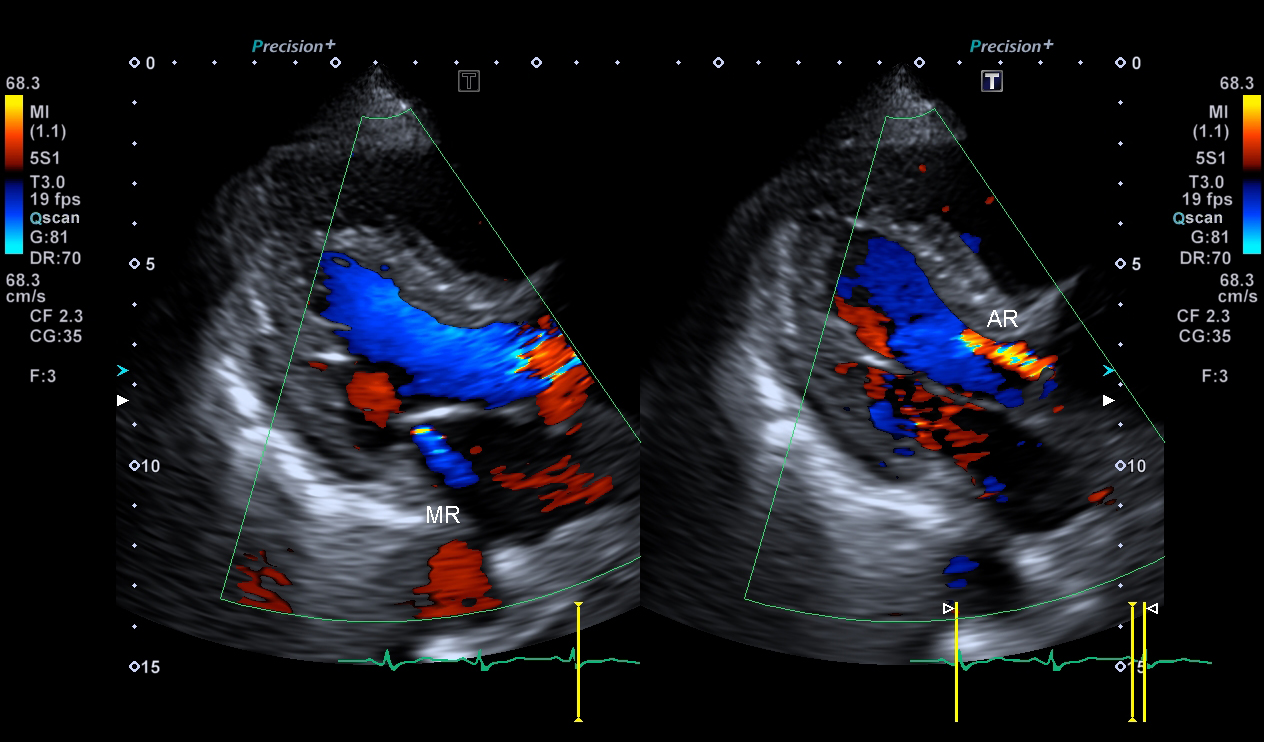

超音波(エコー) 診断画像

- 心エコー(大動脈弁・僧帽弁閉鎖不全症)